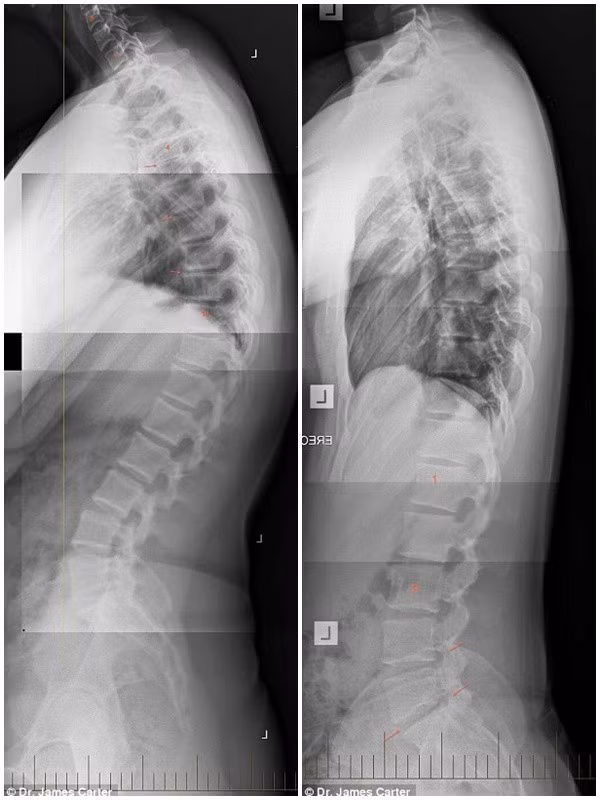

Đây là hình chụp X -quang xương sống của một thiếu niên 20 tuổi nghiện smartphone, tình trạng xương sống thoái hóa tương tự như một cụ ông 80 tuổi.